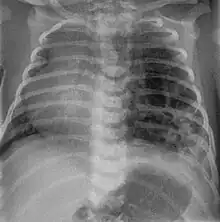

CPAM on chest radiograph in a newborn. Large cystic changes in the left lung, leading to a mediastinal shift to the right due to their mass effect.